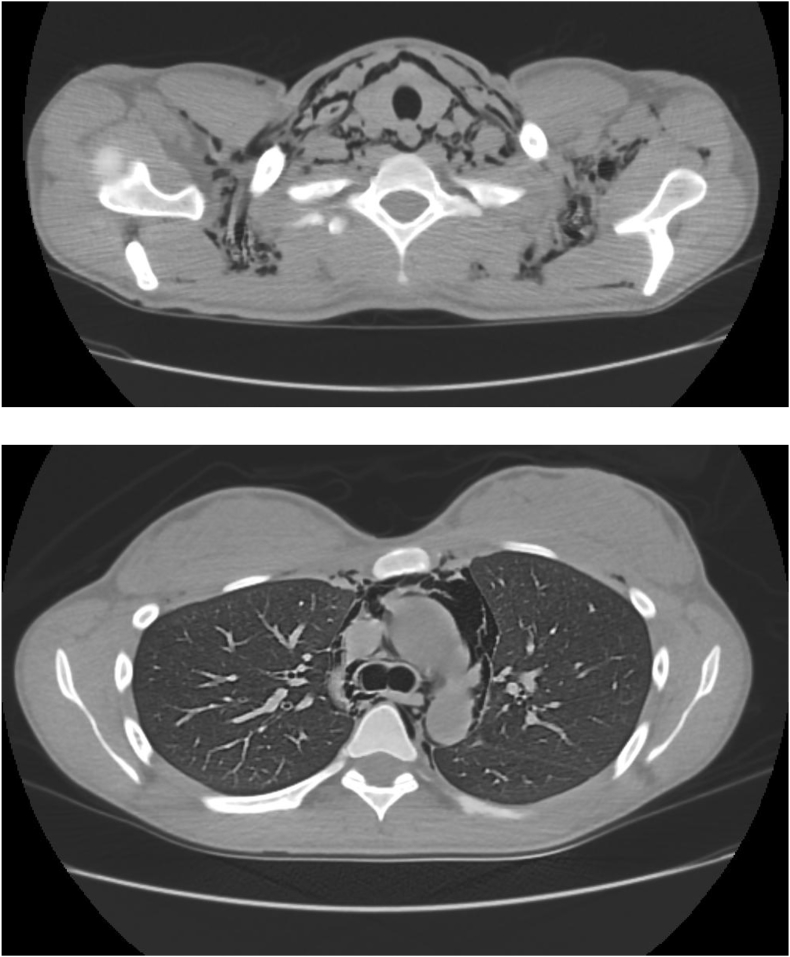

Computerized tomography (CT) scan of the neck and chest revealed extensive pneumomediastinum and soft tissue emphysema in the neck and upper chest with some extension into the retroperitoneum (Fig. 2A and B).

Fig. 2.

A, B: CT scan of Neck and Chest showing soft tissue emphysema in the neck and extensive pneumomediastinum.